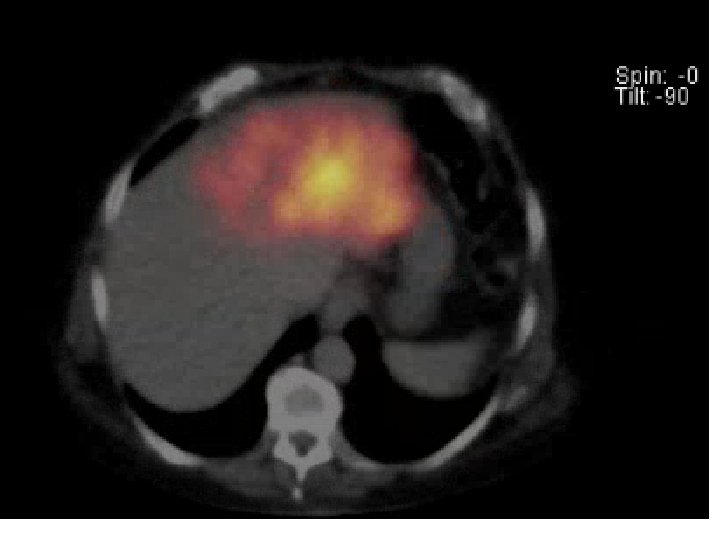

Pre-SIRT